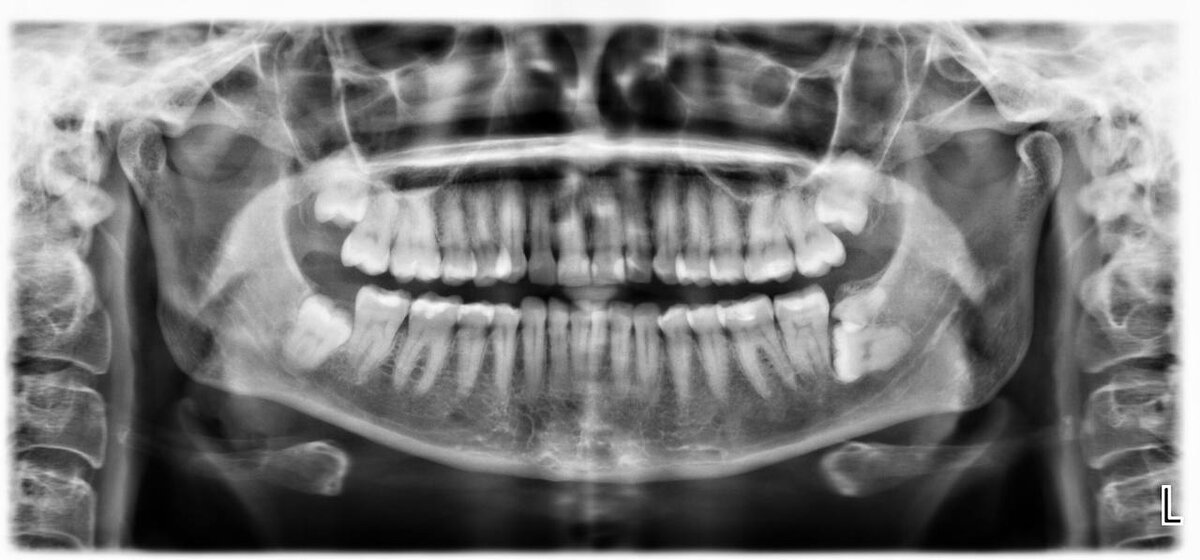

Справа снизу на диагностическом снимке ОПТГ  видим сверхкомплектный 9й зуб

Определить непрорезавшиеся лишние зубы и изучить строение, расположение, форму, размеры можно посредством снимка ОПТГ. Также по результатам обследования лечащий врач может составить полную клиническую картину патологии и назначить дальнейшее лечение.